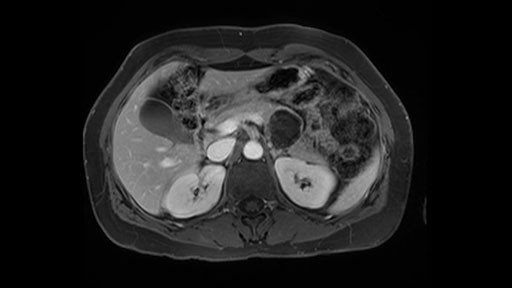

So first, I'll show you the scan. Here's the traditional view, where you see the cyst, which is in the body of the pancreas. And you see over here, it's got a quite thick wall. And going a little bit back also, here you see a septation which is very important, because I think a septation is what separates this from, for instance, the pseudocyst of the pancreatitis. And also the location of the cyst you see here, abutting the adrenal gland and going down a bit more, it's also quite close to a bowel loop. So when thinking about this cyst: female, the location in the body of the pancreas, thick wall, septation, and as you can read in history, it was basically asymptomatic, so no signs of pancreatitis. So, this probably all points towards a mucinous cystic neoplasm.

Key features that I look at the imaging are: first I look at the distance between the cyst and the portal vein SMV confluence. So there are guidelines for this, they call the Yonsei guidelines, to decide to do it laparoscopically or open and basically it says that if it’s a cancer, at least a centimeter away from the celiac trunk or the venous confluence. This is a cyst. So maybe you could stretch that a bit, but you don't want to get into trouble there. So for this cyst if you look at it, it's nicely away from the confluence.

So unfortunately I cannot show you a coronal view but you can see it easily on this scan, going down first you see the celiac trunk and you see here, quite a nice distance between the celiac trunk and the beginning of the mucinous cyst. And if you go up here and follow down the portal vein confluence you also see a nice distance there.

So what I would normally do in these patients, I would look at the abutment of any other organs, one, which is here, potentially the adrenal gland and two the small bowel. And two, look at the distance from the vessels which I would normally do in a coronal view. So you can easily measure the distance and third I look at the insertion of the inferior mesenteric vein. Now we can probably also see that on here. Although it's better on a CT scan and it's better on a coronal view, you want to know where the inferior mesenteric vein comes into either the splenic or the SMV, because that is typically a very important slow down moment when you mobilize the lower portion of the pancreas knowing where the inferior mesenteric vein comes in either the splenic vein or the SMV. So those are I think the three most important points for the CT scan.